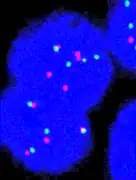

FISH can be used to measure the number of copies of the gene which are present and is thought to be more reliable than immunohistochemistry.[45] It usually uses chromosome enumeration probe 17 (CEP17) to count the amount of chromosomes. Hence, the HER2/CEP17 ratio reflects any amplification of HER2 as compared to the number of chromosomes. The signals of 20 cells are usually counted.

This cell displays 2 signals of HER2 (red) and 3 signals of CEP17 (green)

Two signals that are closer to each other than the signal diameter count as one.

One of these signals is too faint, and is presumably debris.

Cells with only one type of signal are excluded from the count.

Overlapping cells are also excluded from the count.

A yellow signal counts as one red and one green (which are overlapping)